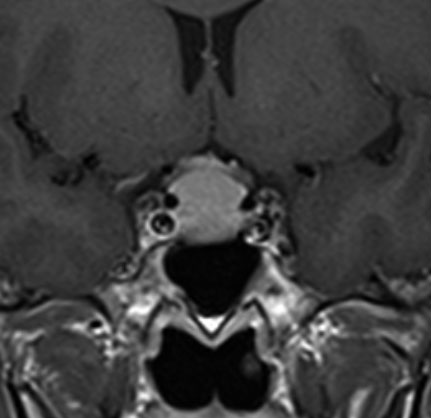

大後頭孔(大孔)髄膜腫 foramen magnum meningioma)

この腫瘍はfarlateral approachなどの頭蓋底手術をしなくても,外側後頭窩開頭で全摘出できます。要領は,S状静脈洞の下端の周囲骨を削除することです。大後頭孔髄膜種は延髄を圧迫するので巨大なものはありません。出血のコントロールや延髄からの剥離は比較的容易なものが多いでしょう。舌咽神経と迷走神経損傷を避けることが重点となります。

迷走神経と舌咽神経は機能温存できました。舌下神経が腫瘍の表面に薄く広がり剥がすことができずに半分以上を切断しています。でも片側舌下神経麻痺では日常生活に困ることはあまりありません。